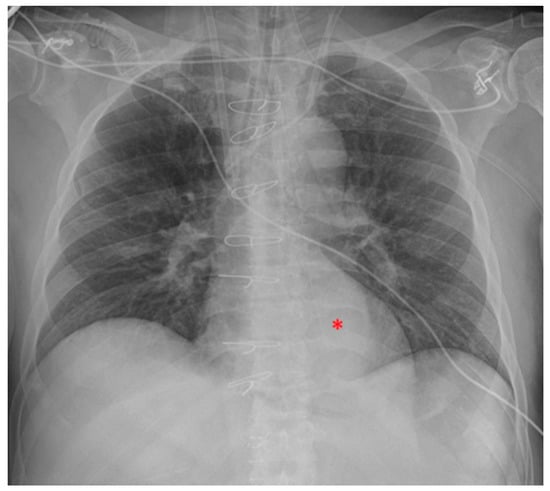

5.5. Intra-Aortic Balloon Pump (IABP)

5.6. Extracorporeal Membrane Oxygenation (ECMO)